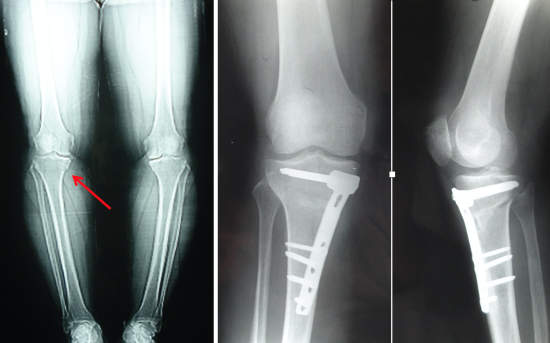

Joint preserving surgery encompasses a variety of procedures that aim to restore or reconstruct the damaged parts of the joint. If the alignment of your leg is abnormal, a procedure called an “osteotomy” may be performed to unload the damaged compartment. One or two bones in the leg are cut, re-aligned and fixed with screws and plates during an osteotomy (Picture 1). This usually is a first step of joint preservation if your leg alignment is unfavorable and is mostly performed around the knee joint. An “osteoplasty” can be performed in the hip joint in patients with impingement syndrome. This is a procedure in which the impinging bone prominence is removed to prevent cartilage and labrum damage and is usually performed arthroscopically.